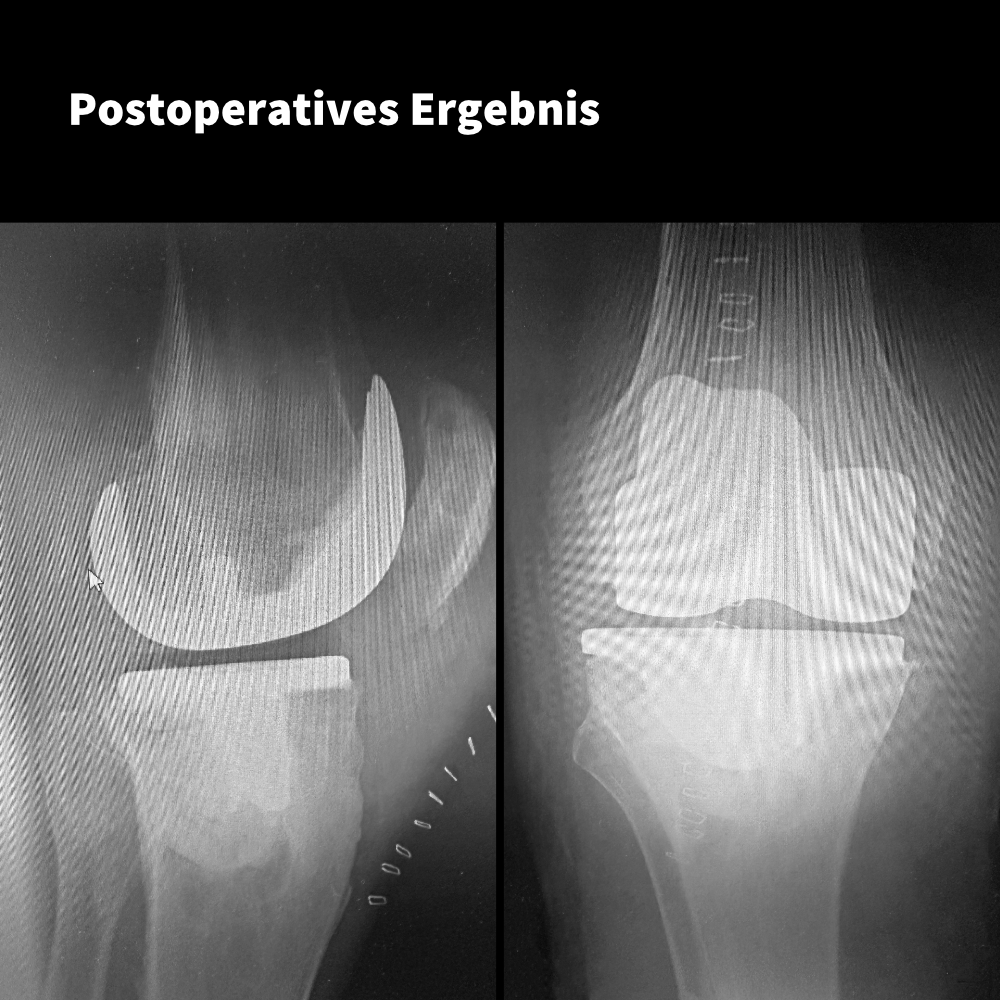

Knie-TEP mit dem 4-motion® Kniesystem bei Pangonarthrose und Knochenzysten

Ein Fall von: Dr. Jens Peters, Kliniken Landkreis Diepholz, Sulingen

Der Patient: Männlich, 60 Jahre